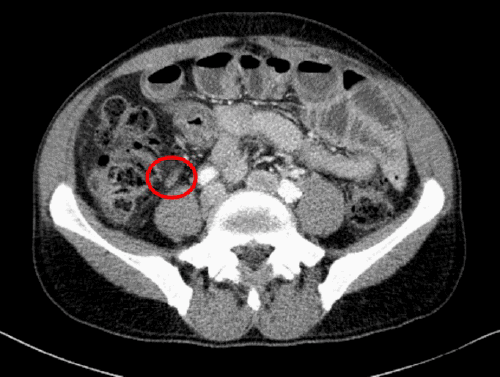

This case demonstrates an exceptionally atypical presentation, as the absence of abdominal pain complaints obscured the timeline of his illness. Retrospective review of imaging confirmed a retrocecal position of the appendix (Figure 4), which predisposed him to the formation of a contained retroperitoneal perforation, fistula, and subsequent massive abscess. This insidious process, coupled with his undiagnosed medical comorbidities and florid sepsis, culminated in a near-fatal outcome. The management strategy of interval appendectomy following initial source control with percutaneous drainage and antibiotic therapy is well-described for contained perforations with abscess formation. While some studies suggest little difference in surgical complications between early and delayed laparoscopic appendectomy,7 in this critically ill patient with an unclear initial etiology, a staged approach was a clinical necessity rather than an elective choice.

Figure 4. Retrospective CT Confirming Retrocecal Appendix. Published with Permission

Axial view from a prior CT scan from 2017. This image retrospectively confirms the retrocecal position of the patient’s normal-appearing appendix (arrow), demonstrating its close proximity to the right psoas muscle, which explains its predisposition to form a contained retroperitoneal perforation